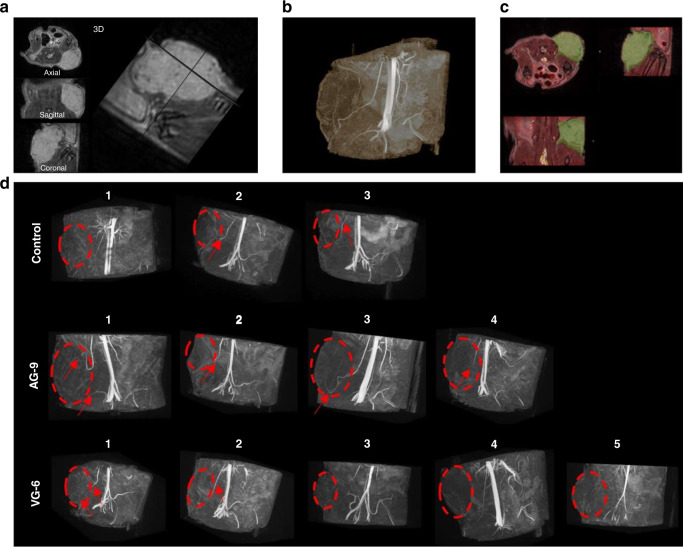

Tumour vascularisation and the impact of elastin-derived peptides on angiogenesis

Tumour vascularisation was assessed by 3D MR angiography in vivo, showing penetrating patent vessel in tumours (Fig. 6a, c). From the MRA, we could identify mature vessels ending in close vicinity of the tumour in all groups. Only in the AG-9 group, these mature vessels are penetrating the tumour in three out of four animals. Interestingly, the only animal in which we could not detect penetrating mature vessels from MR angiography data is the one with the smallest tumour volume (244.6 mm3 compared to 533–646 mm3 for the tumours in the three other animals) (Fig. 6d).

Fig. 6. 3D MRI angiography for in vivo assessment of the effect of elastin-derived peptide on tumour vascularisation and tumour growth.

a 3D T2-weighted RARE of the tumour and b its corresponding 3D TOF MRA maximum intensity projection with the blue arrow pointing to a penetrating patent vessel. Both 3D volumes are spatially co-registered. c (Overlay of anatomical 3D in greyscale and 3D TOF MRA in hot colour) and tumour were segmented (green overlay). d 3D TOF MRA patent arteries (red arrows) reached the vicinity of the tumour (red dashed circle, based on T2-weighted anatomical MRI) and penetrate inside the tumour in some cases.